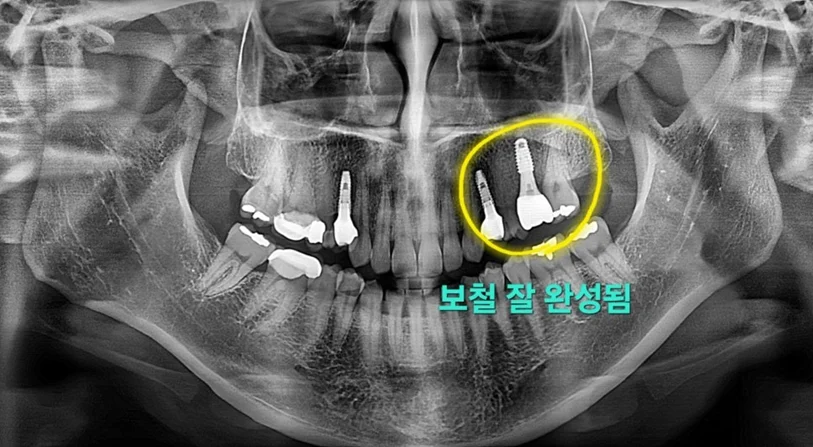

임플란트를 올바른 위치와 적절한 직경으로 재식립하였고, 상악동 거상술과 뼈이식이 모두 잘 마무리되었습니다.

이후 골유착이 완성된 뒤 보철을 제작했으며, 환자분께서도 튼튼하게 완성된 임플란트에 충분히 만족하셨습니다.

▲ 최종 보철 완성 후 구강 사진